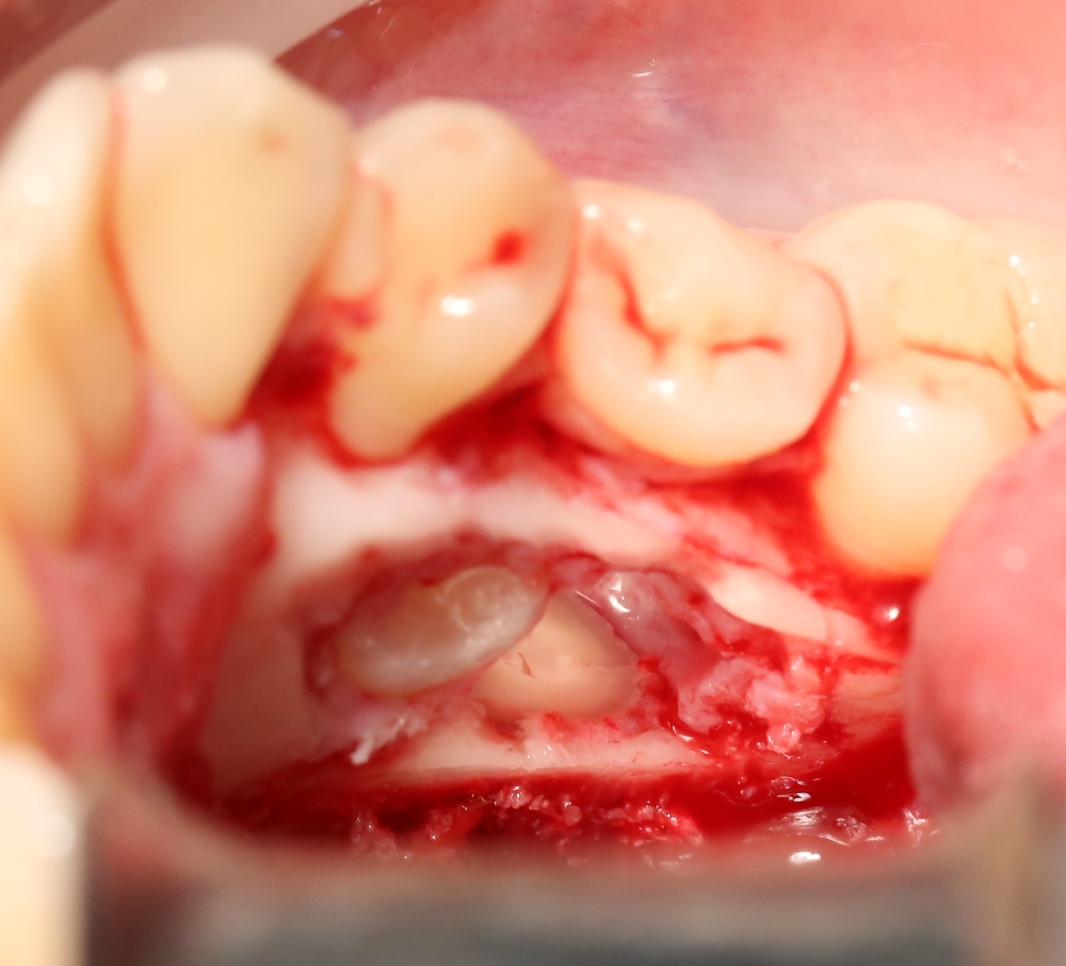

А вот их лунки:

Теоретически, лунки можно чем-нибудь заполнить. Только чем? И для чего?

Костная ткань сама регенерирует, если ей не мешать. Поэтому не стоит толкать в лунки какой-нибудь остеопластический материал, типа Cerabone или Bioss. Нет смысла.

В данном случае я использовал обычную коллагеновую губку — и то, только для того, чтобы «костная дверца», которую я выпилил в самом начале операции, не провалилась внутрь:

Теперь запиливаем «костную дверцу» на ее законное место:

И накладываем швы.